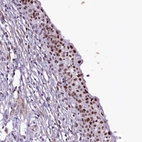

Immunohistochemical staining of human urinary bladder shows strong nuclear positivity in urothelial cells.